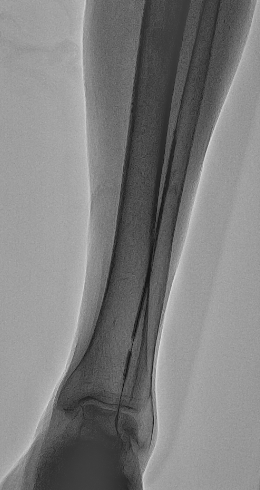

造影术中顺左股动脉走向穿刺,置入6F鞘管,造影提示“左股浅动脉中远段完全闭塞(图1),可见明显钙化影,左股深动脉可见侧枝至左腘动脉;左胫前动脉近段完全闭塞(图2),左胫后动脉开口完全闭塞,左腓动脉近段闭塞,左胫前动脉近段侧枝至左腓动脉中段,左腓动脉中段至足背动脉轻度狭窄,血流缓慢”。

图2 左胫前动脉近段闭塞